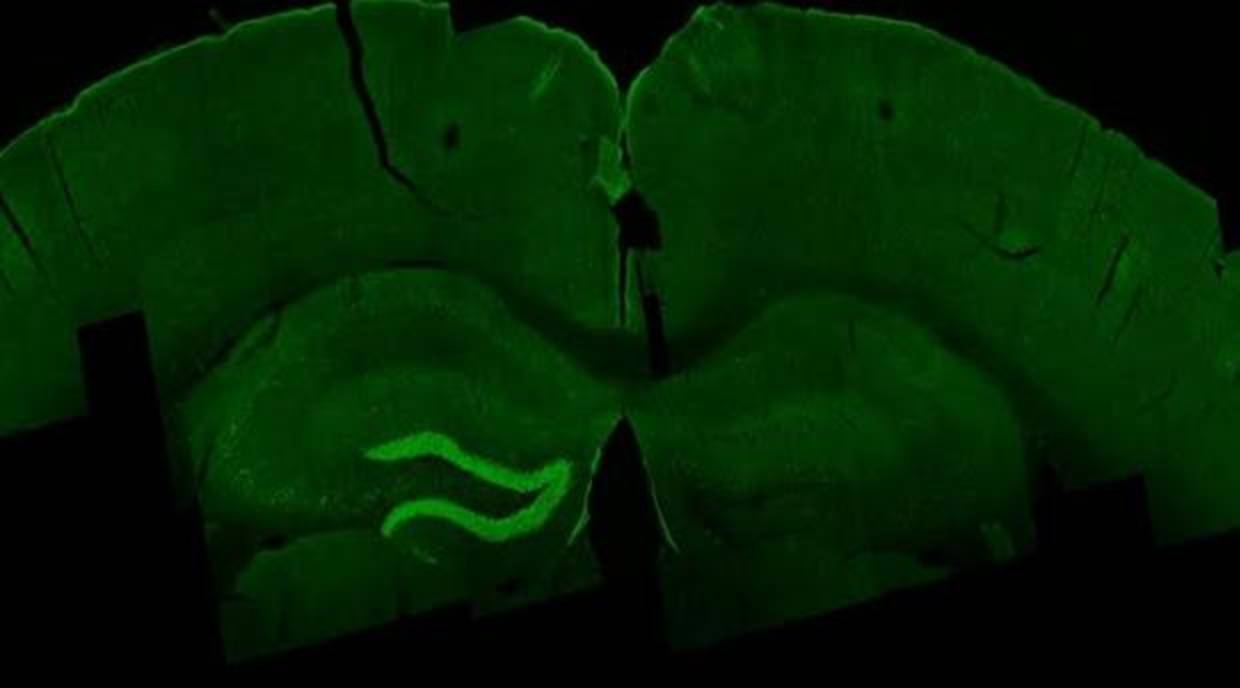

Estimulación con la ETI del hipocampo (en verde) de un ratón MIT

Concretamente, el estudio, publicado en la revista « Cell », describe una nueva técnica que, denominada ‘estimulación de interferencia temporal’ (EIT), es capaz de inducir el movimiento de las patas, orejas y bigotes en ratones con la simple imposición de electrodos sobre el cráneo. Una técnica que, en opinión de los autores, abre una nueva vía muy prometedora en la investigación de los trastornos neurológicos –y por qué no, en su posible tratamiento.